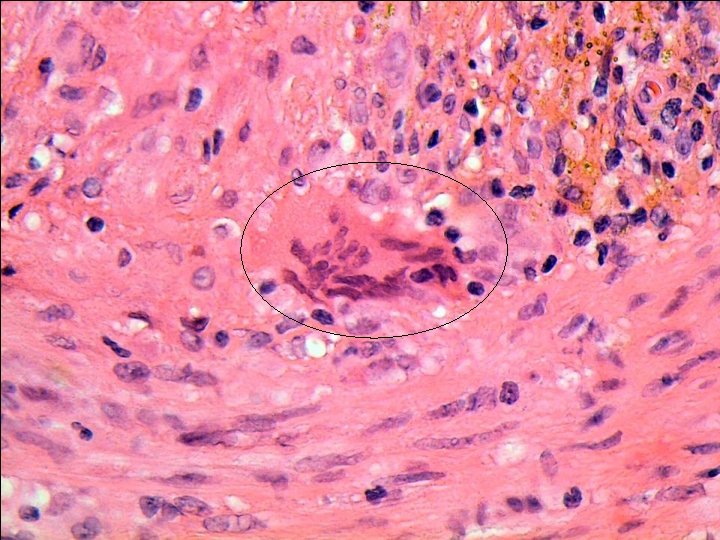

Temporal arteritis Idiopathic, granulomatous vasculitis of large or medium sized elastic arteries. SKIP LESIONS Predilection for superficial temporal artery, but can affect cerebral arteries, carotids, coronary arteries, aorta, renal arteries etc… Pathogenesis-actinically damaged elastic tissue-trigger cell-mediated immune response ? Infection? Histology-with and without giant cells. Adventitial acute and chronic inflammation with involvement of media (muscle layer). Fragmentation of internal elastic lamina. Giant cells at sites of internal elastic lamina rupture (not always). Inflammatory oedema of intima, with stenosis of lumen.